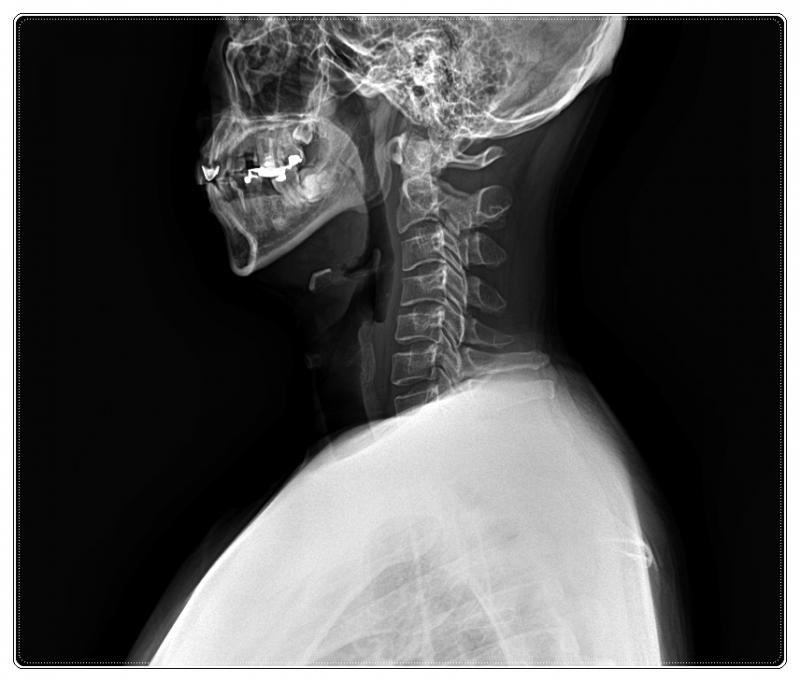

목디스크 수술 후 재활, 왜 다시 불편해질까요

• 틀어진 목뼈와 턱관절 위치 점검

이처럼 구조적인 균형이 맞아야 디스크에 가해지는 압력을 줄일 수 있기 때문입니다.

목 통증이 있더라도 어깨, 골반, 전반적인 자세와 생활 습관까지 함께 살피며 몸의 균형을 확인합니다.

이에 따라 목 주변 근육과 신경 상태뿐 아니라,

척추 정렬과 내장 기능의 균형까지 함께 고려하며 재활을 진행합니다.